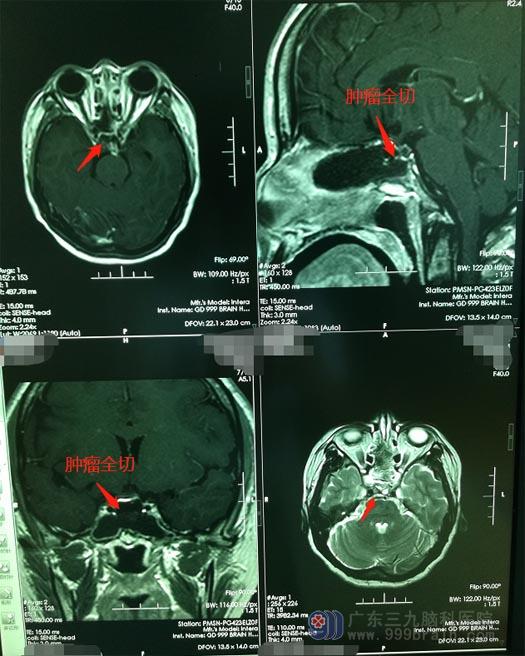

患者手术指征明确,鲁明带领神经外五科手术团队在全麻下为何女士行“内镜经鼻碟鞍区占位切除术+颅底重建术”。术中导航定位,小心分离蝶窦粘膜,磨除鞍底及鞍结节骨窗约1.5cm大小,切开鞍底硬膜,可见垂体肿胀,纵行切除垂体可见乳白色囊液流出并有结晶,予以全部切除,止血,修复鞍底,生物蛋白胶密封鞍底,双侧鼻腔填塞膨胀海绵止血。手术过程顺利。

术后,何女士没有出现手术并发症及后遗症,几天后便康复出院了。